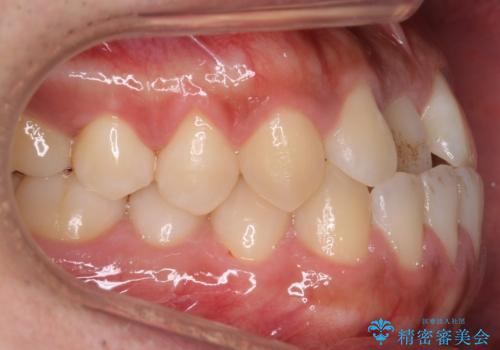

骨格性の受け口の矯正 部分ワイヤーで上の前歯を前に、 マウスピースで下の前歯を後ろに。

- 受け口を主訴に来院。

前歯のかみ合わせが逆になり上の前歯が奥に入っていました。

前歯を前に乗り越えさせるのは、ワイヤー矯正が一番早く歯に負担がかかりにくいです。